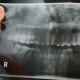

Mhn opini mengenai pasien dg panoramic seperti ini....M1 di kedua sisi sudah mengalami penambalan 1x, dg gambaran seperti ini, apakah bisa M1 yg kita cabut atau harus P1 saja? Karena pasiennya ingin memberi space dari gigi yg sudah rusak saja, tidak mencabut yg masih bagus. Mhn arahan, Dok...terimakasih.